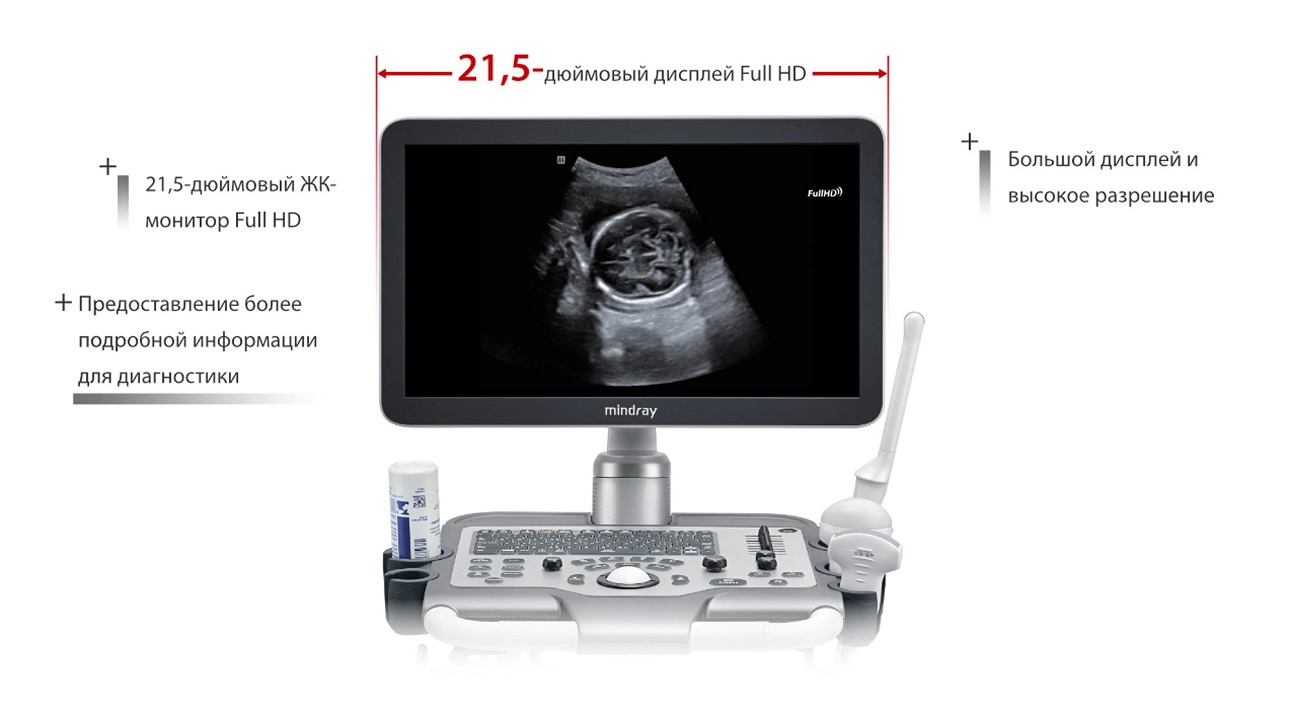

Уровень FullHD

21,5-дюймовый экран:

1920 x 1080, вращение на 180°

Уровень FullHD

2

21,5-дюймовый экран: 1920 x 1080, вращение на 180°